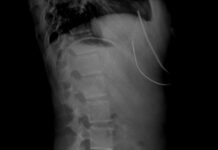

“손이 자꾸 저려요”… 거북목보다 위험한 ‘흉곽출구증후군’

“컴퓨터 할 때마다 오른팔이 저릿저릿해요.”IT회사에 다니는 34세 김나연 씨는 어느 날부터인가 마우스를 오래 쓰면 팔이 저리고, 손끝 감각이 둔해지는 경험을 한다. 자세가 문제일까 싶어...